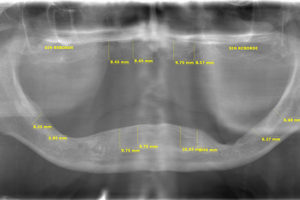

MEDICIONES PARA PRÓTESIS E IMPLANTES DENTALES

Este procedimiento se lo realiza sobre la radiografía panorámica, de senos maxilares y tomografía 3D, nuestro moderno software permite tener una medición exacta de rebordes maxilares, información requerida para colocación de prótesis e implantes.